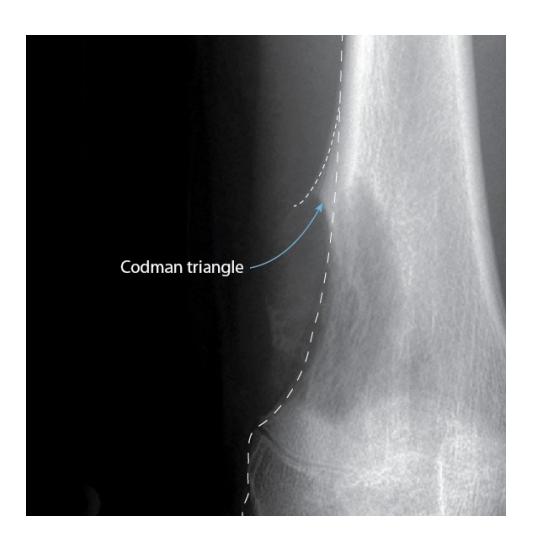

Codman’s triangle- causes include infections / tumours

site: distal femur size: Most (involving how much? / cm?) matrix: mixed - mainly radiopaque , wide zone of transition, cortical destruction, resulted periosteal reaction, and codman’s triangle soft tissue involvement: